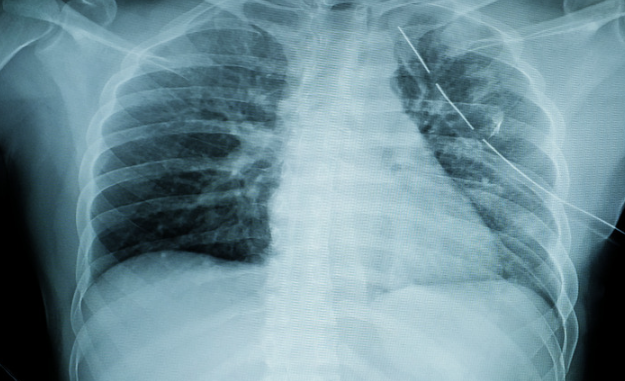

The shoulder belt can put significant pressure on the chest during a crash, and that pressure can fracture the ribs or the sternum (breastbone). Rib fractures are painful and can make breathing difficult. Sternal fractures are less common but can indicate more serious trauma.

Seat belts can compress the abdomen during a crash, which can lead to damage to internal organs such as the liver, spleen, kidneys, bowels, or pancreas. These injuries may not be visible at first, but can be life-threatening if not treated. Internal abdominal trauma is often part of “seat belt syndrome.”

The shoulder belt can exert force on the torso and neck. This can strain the spine or even lead to vertebral fractures in severe cases. Some types of spinal fractures, like Chance fractures, occur when the body bends excessively under force.

Since many seat belt injuries are internal, a quick physical exam at the scene isn’t always enough. In an ER or urgent care setting, medical teams use a specific toolkit to see what’s happening beneath the surface: